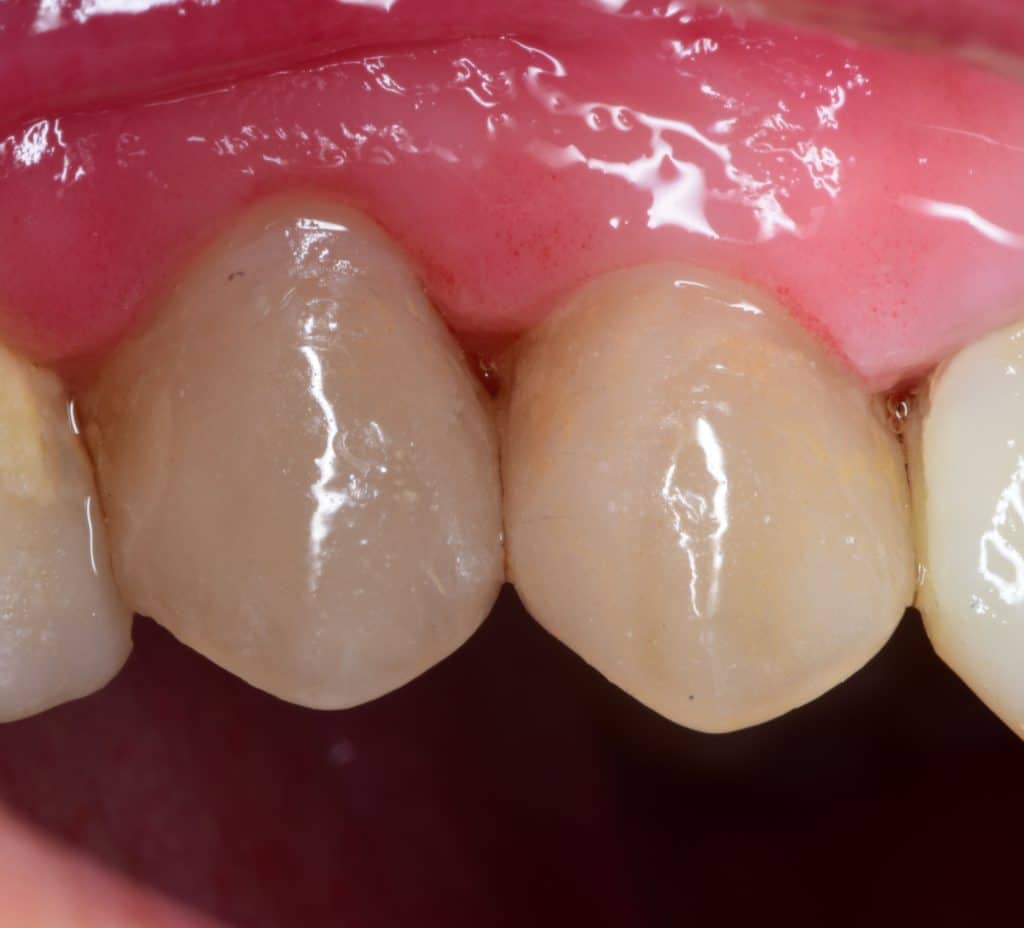

Initial situation showing large carious lesion in the upper premolars

Buccal view showing the extension of the caries

2 weeks later, healing of the soft tissue 💙

Buccal view, look to the healing